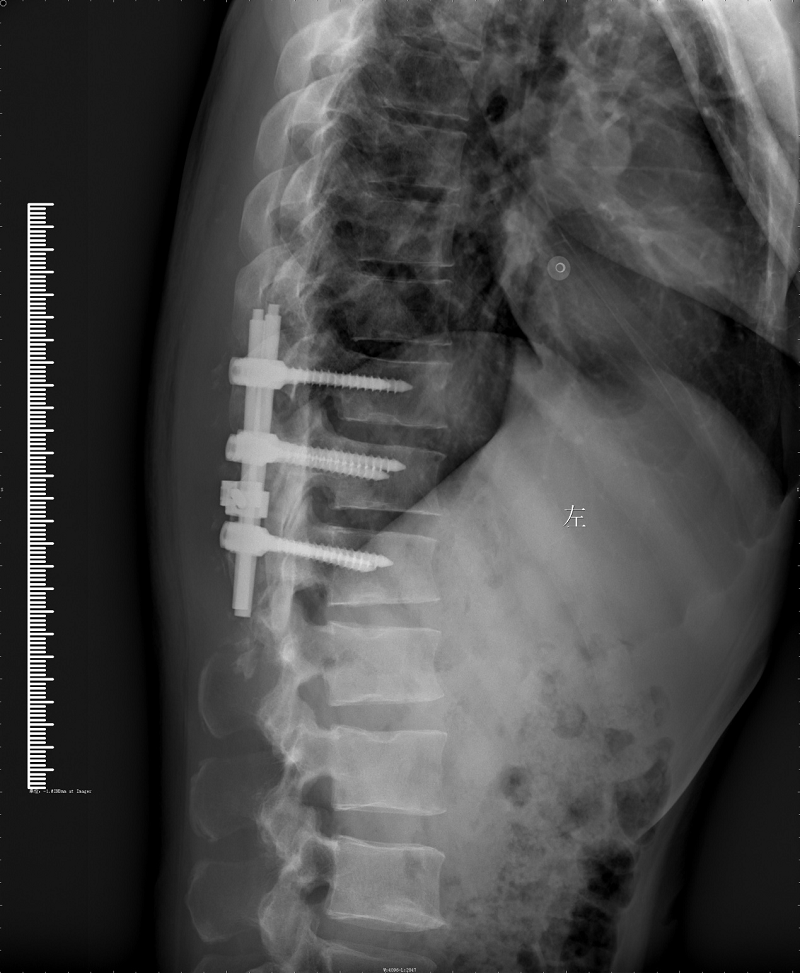

病史:患者中年男性;起病缓,病程长;以"腰背疼痛4年伴双下肢麻木无力进行性加重1年。"为主要表现,查体:查体:神清,腰背部:胸椎10-骶椎皮肤可见"艾交"瘢痕,椎体棘突广泛压痛,腹壁反射存在,腹股沟平面以下可见深浅感觉明显减退,以右侧为甚,疼痛刺激明显降低,肌力Ⅲ级,肌张力不高,病理征阴性,鞍区感觉降低,提睾反射存在;我院MRI示:1.腰椎退变;2.腰椎多个椎体许莫结节形成;3.胸10-腰1椎管内硬脊膜下见梭形片团状混杂稍长T1和稍长T2信号,脊髓向右推及变细,肿瘤性病变?其他?完善术前检查于全麻下经后路椎管内病变切除术+椎管降压术+后路内固定,术后予抗感染,止血,营养神经,请康复科康复训练,经治疗后患者现生命体征平稳,切口愈合I/甲,未见溢液及脑脊液漏,双下肢肌力左侧3-级,右侧肌力3+级,肌张力不高,感觉左侧下降至膝关节平面,右侧踝关节平面,术后3月复查患者扶拐行走。

术后脊椎: